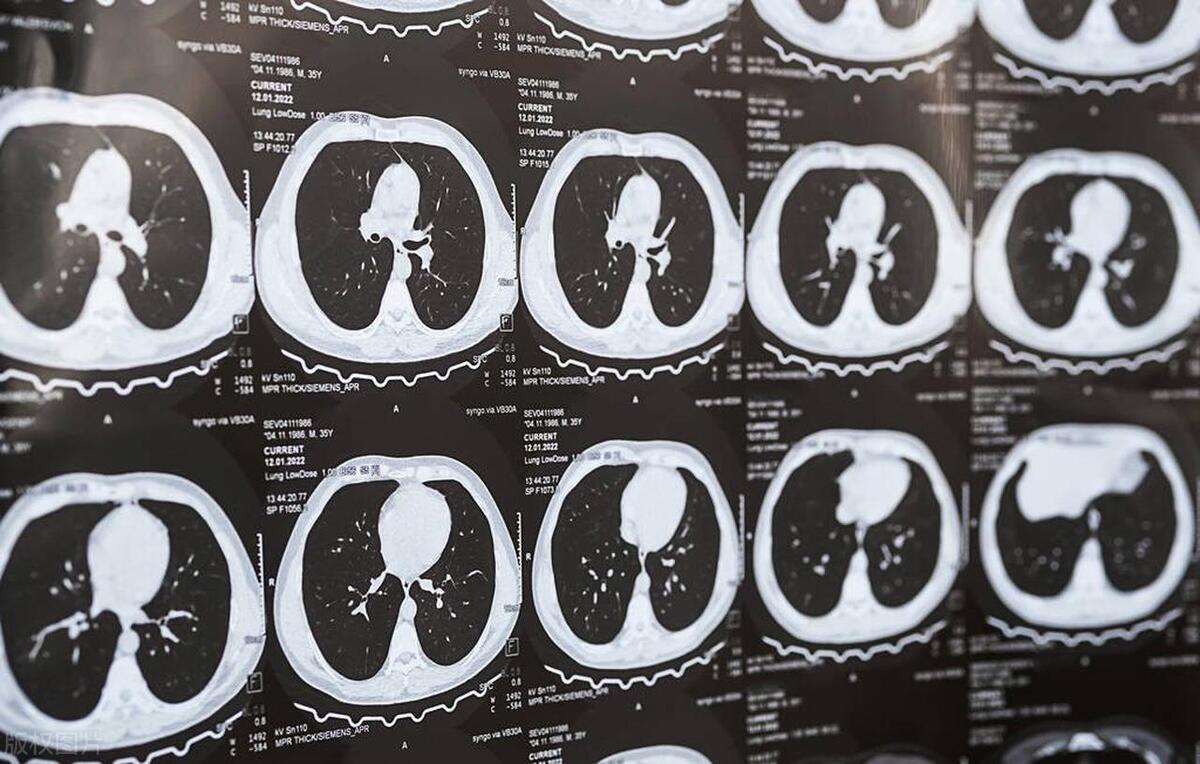

以前,我们认为原位癌是“坏的”,一定要立即切除。实际上,肺原位癌在CT下的表现通常为5~30毫米纯磨玻璃结节,密度均匀,CT值在-600以下,无血管进入。从长期的观察来看,尽管这种病变发生了,但它并未向其他组织扩散,安全性相对较高且恶性度较低。大多数肺原位癌的生长极其缓慢,70%~80%可长期稳定,只有10%会朝微浸润腺癌发展。

怎么样才算是微浸润肺腺癌?微浸润肺腺癌在影像学上多数表现为纯磨玻璃结节,也有部分表现为部分实性结节,极少数表现为实性结节。在纯磨玻璃结节中,结节的直径及特殊影像征象的有无决定结节的浸润性;而对于部分实性结节,根据其内实性成分的比例来区分浸润前病变和浸润性腺癌至关重要。

通常对照病理报告来说,在纯磨玻璃结节中,直径≥10 mm就需要引起注意了,另外可以根据CT值、分叶征、胸膜牵拉和支气管充气征等特殊影像征象辅助判断;在混合磨玻璃结节中,实性最大径一般≤5mm,CT值为负500左右,总体实性占比总体的四分之一时,同样需要警惕。